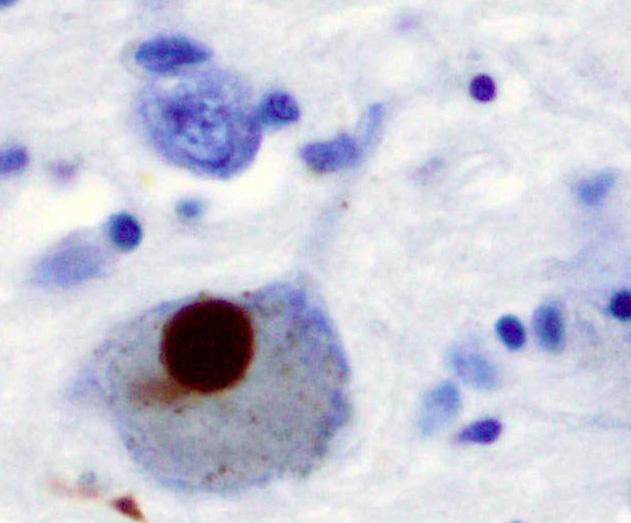

The primary neurological hallmark of the disease is the formation of so-called Lewy bodies--microscopic aggregates of a protein known as α-synuclein. Lewy bodies are involved in other neurological disorders as well, including dementia with Lewy bodies (DLB). Evidence suggests that dementia with Lewy bodies, Parkinson's disease and Parkinson's disease dementia may all be related to abnormalities in brain processing of α-synuclein.

Caption:Brain image from the Substantia nigra in Parkinson's disease, showing alpha-synuclein, a key protein implicated in the disease. Positive staining (brown) indicates an intraneural Lewy-body. Credit:Marvin 101